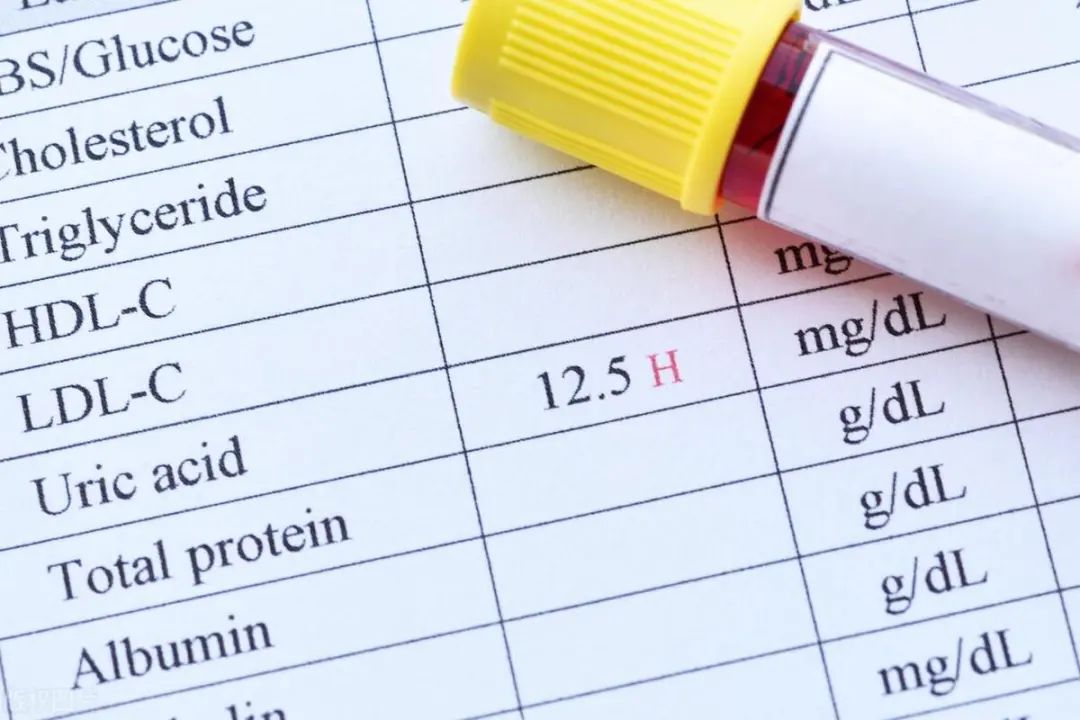

04/X线检查

早期的痛风性关节炎X线检查关节无明显改变;痛风反复发作到中后期,有典型的X线表现:尿酸盐结晶在骨质中沉积,对骨质产生凿孔样、虫蚀样破坏,缺损多呈圆形或弧形改变,可有骨疣生成,局部可有骨质疏松改变,病变周围骨质可有增生,且界限清晰,边缘锐利,“鼠咬式损害”有利于与其他关节病相鉴别。

04/其他影像学检查

除了以上的检查外,还有肌骨超声、关节B超、核磁共振等影像学检查,这对早期发现尿酸盐在关节处的结晶沉积、明确关节和骨骼的损伤程度、评估慢性滑膜炎等都有必要,并且对正确诊断和判断痛风病情轻重起了重要的作用。